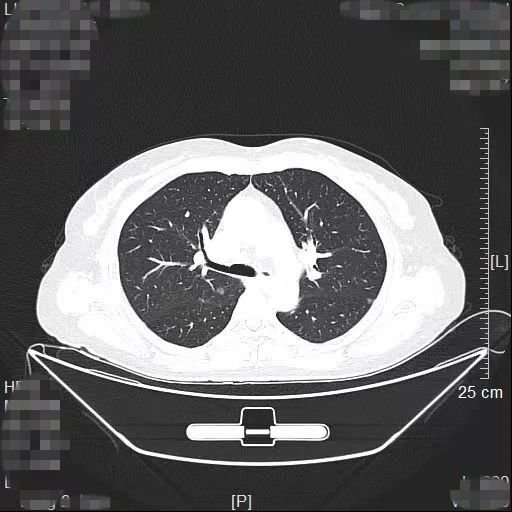

患者林女士今年65岁,长期旅居国外的她在回国后常规体检时查出右肺有2个高危的磨玻璃结节,慕名找到我院胸部肿瘤外科方卫民主任医师。医生团队详细分析了患者的肺部CT及三维重建结果,发现2个结节分别位于右上肺后段边缘及右中肺叶中央,如果直接采用手术切除的方法,要多切除整个右肺中叶,将损失较多的正常肺组织,影响生活质量,得不偿失。

三维重建结果

由于患者签证时间将到,无法分次手术,医生团队经过反复讨论,最终为患者量身定做了“针孔消融+单孔微创”的杂交手术方案。首先在医院肿瘤与血管微创介入治疗中心CT引导下为患者右中肺叶结节进行热消融治疗,仅仅一个针眼;接着进行单孔胸腔镜亚肺段切除,仅仅一个3cm大小的切口,术中冰冻病理报告:原位腺癌,疑有浸润。顺利为患者解除了肺部的2个健康隐患。